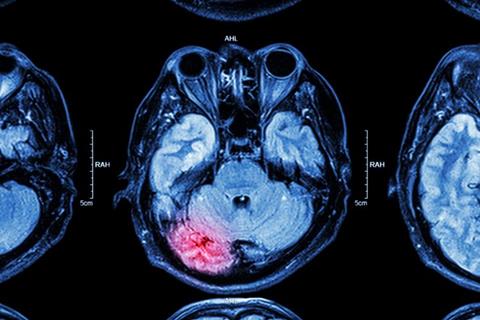

Drug discovery company, TauGen, has filed a US patent application for a new series of drug candidates targeting endoplasmic reticulum (ER) stress – a key factor in secondary brain injury following traumatic brain injury (TBI).

The drug candidates are designed to mitigate "downstream" pathological mechanisms, specifically targeting endoplasmic reticulum (ER) stress – a crucial factor in secondary brain injury following TBI. ER stress is defined by the accumulation of unfolded and misfolded proteins, which research has shown to play a key role in brain cell health and the progression of injury.